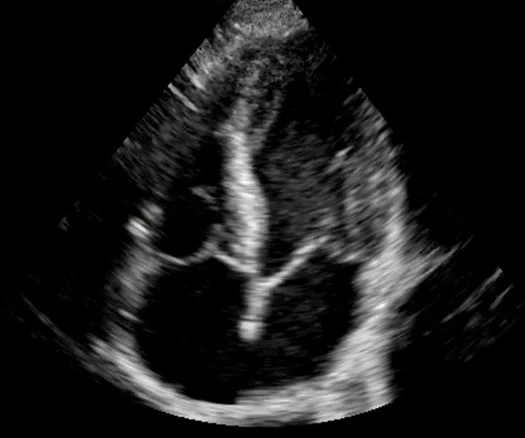

Ultrasound in Cardiac Arrest1. ResusTEE Collaborative (https://www.resuscitativetee.com/collaborative)2. Reason Trial 3 (Echocardiographic vs Electrocardiographic Findings in Cardiac Arrest)

Ultrasound in Cardiac Arrest

1. ResusTEE Collaborative (https://www.resuscitativetee.com/collaborative)

2. Reason Network